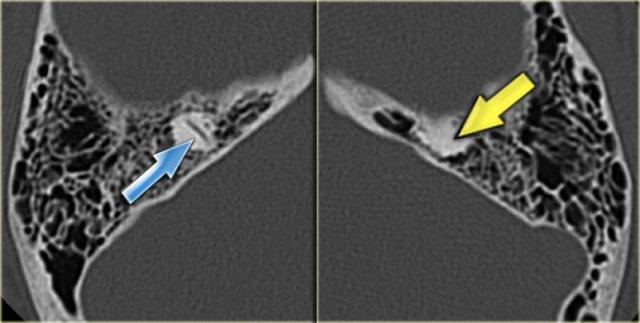

Bên trái là hình ảnh cắt ngang và cắt vành của một bệnh nhân nam 64 tuổi.

Hành tĩnh mạch cảnh nhô lên cao hơn bờ dưới của ống bán khuyên sau (mũi tên).

Hành tĩnh mạch cảnh thường không đối xứng, với hành tĩnh mạch cảnh bên phải thường lớn hơn bên trái.

Khi hành tĩnh mạch cảnh vượt lên trên ống bán khuyên sau, được gọi là hành tĩnh mạch cảnh cao.

Khi vách xương ngăn cách giữa hành tĩnh mạch cảnh và hòm nhĩ bị khuyết, được gọi là hành tĩnh mạch cảnh hở.

Hiếm gặp hơn là hình ảnh túi phình nhỏ – được gọi là túi thừa hành tĩnh mạch cảnh.

Bên trái là hình ảnh cắt ngang và cắt vành của một bệnh nhân nam 50 tuổi.

Phát hiện tình cờ túi thừa hành tĩnh mạch cảnh (mũi tên).